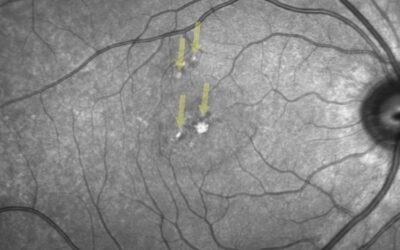

Cas Clinique – le danger invisible des pointeurs laser chez l’enfant

On associe souvent les accidents rétiniens liés aux lasers à une exposition directe. Pourtant, ce cas illustre une réalité plus insidieuse : la dangerosité de la réflexion spéculaire, souvent sous-estimée.